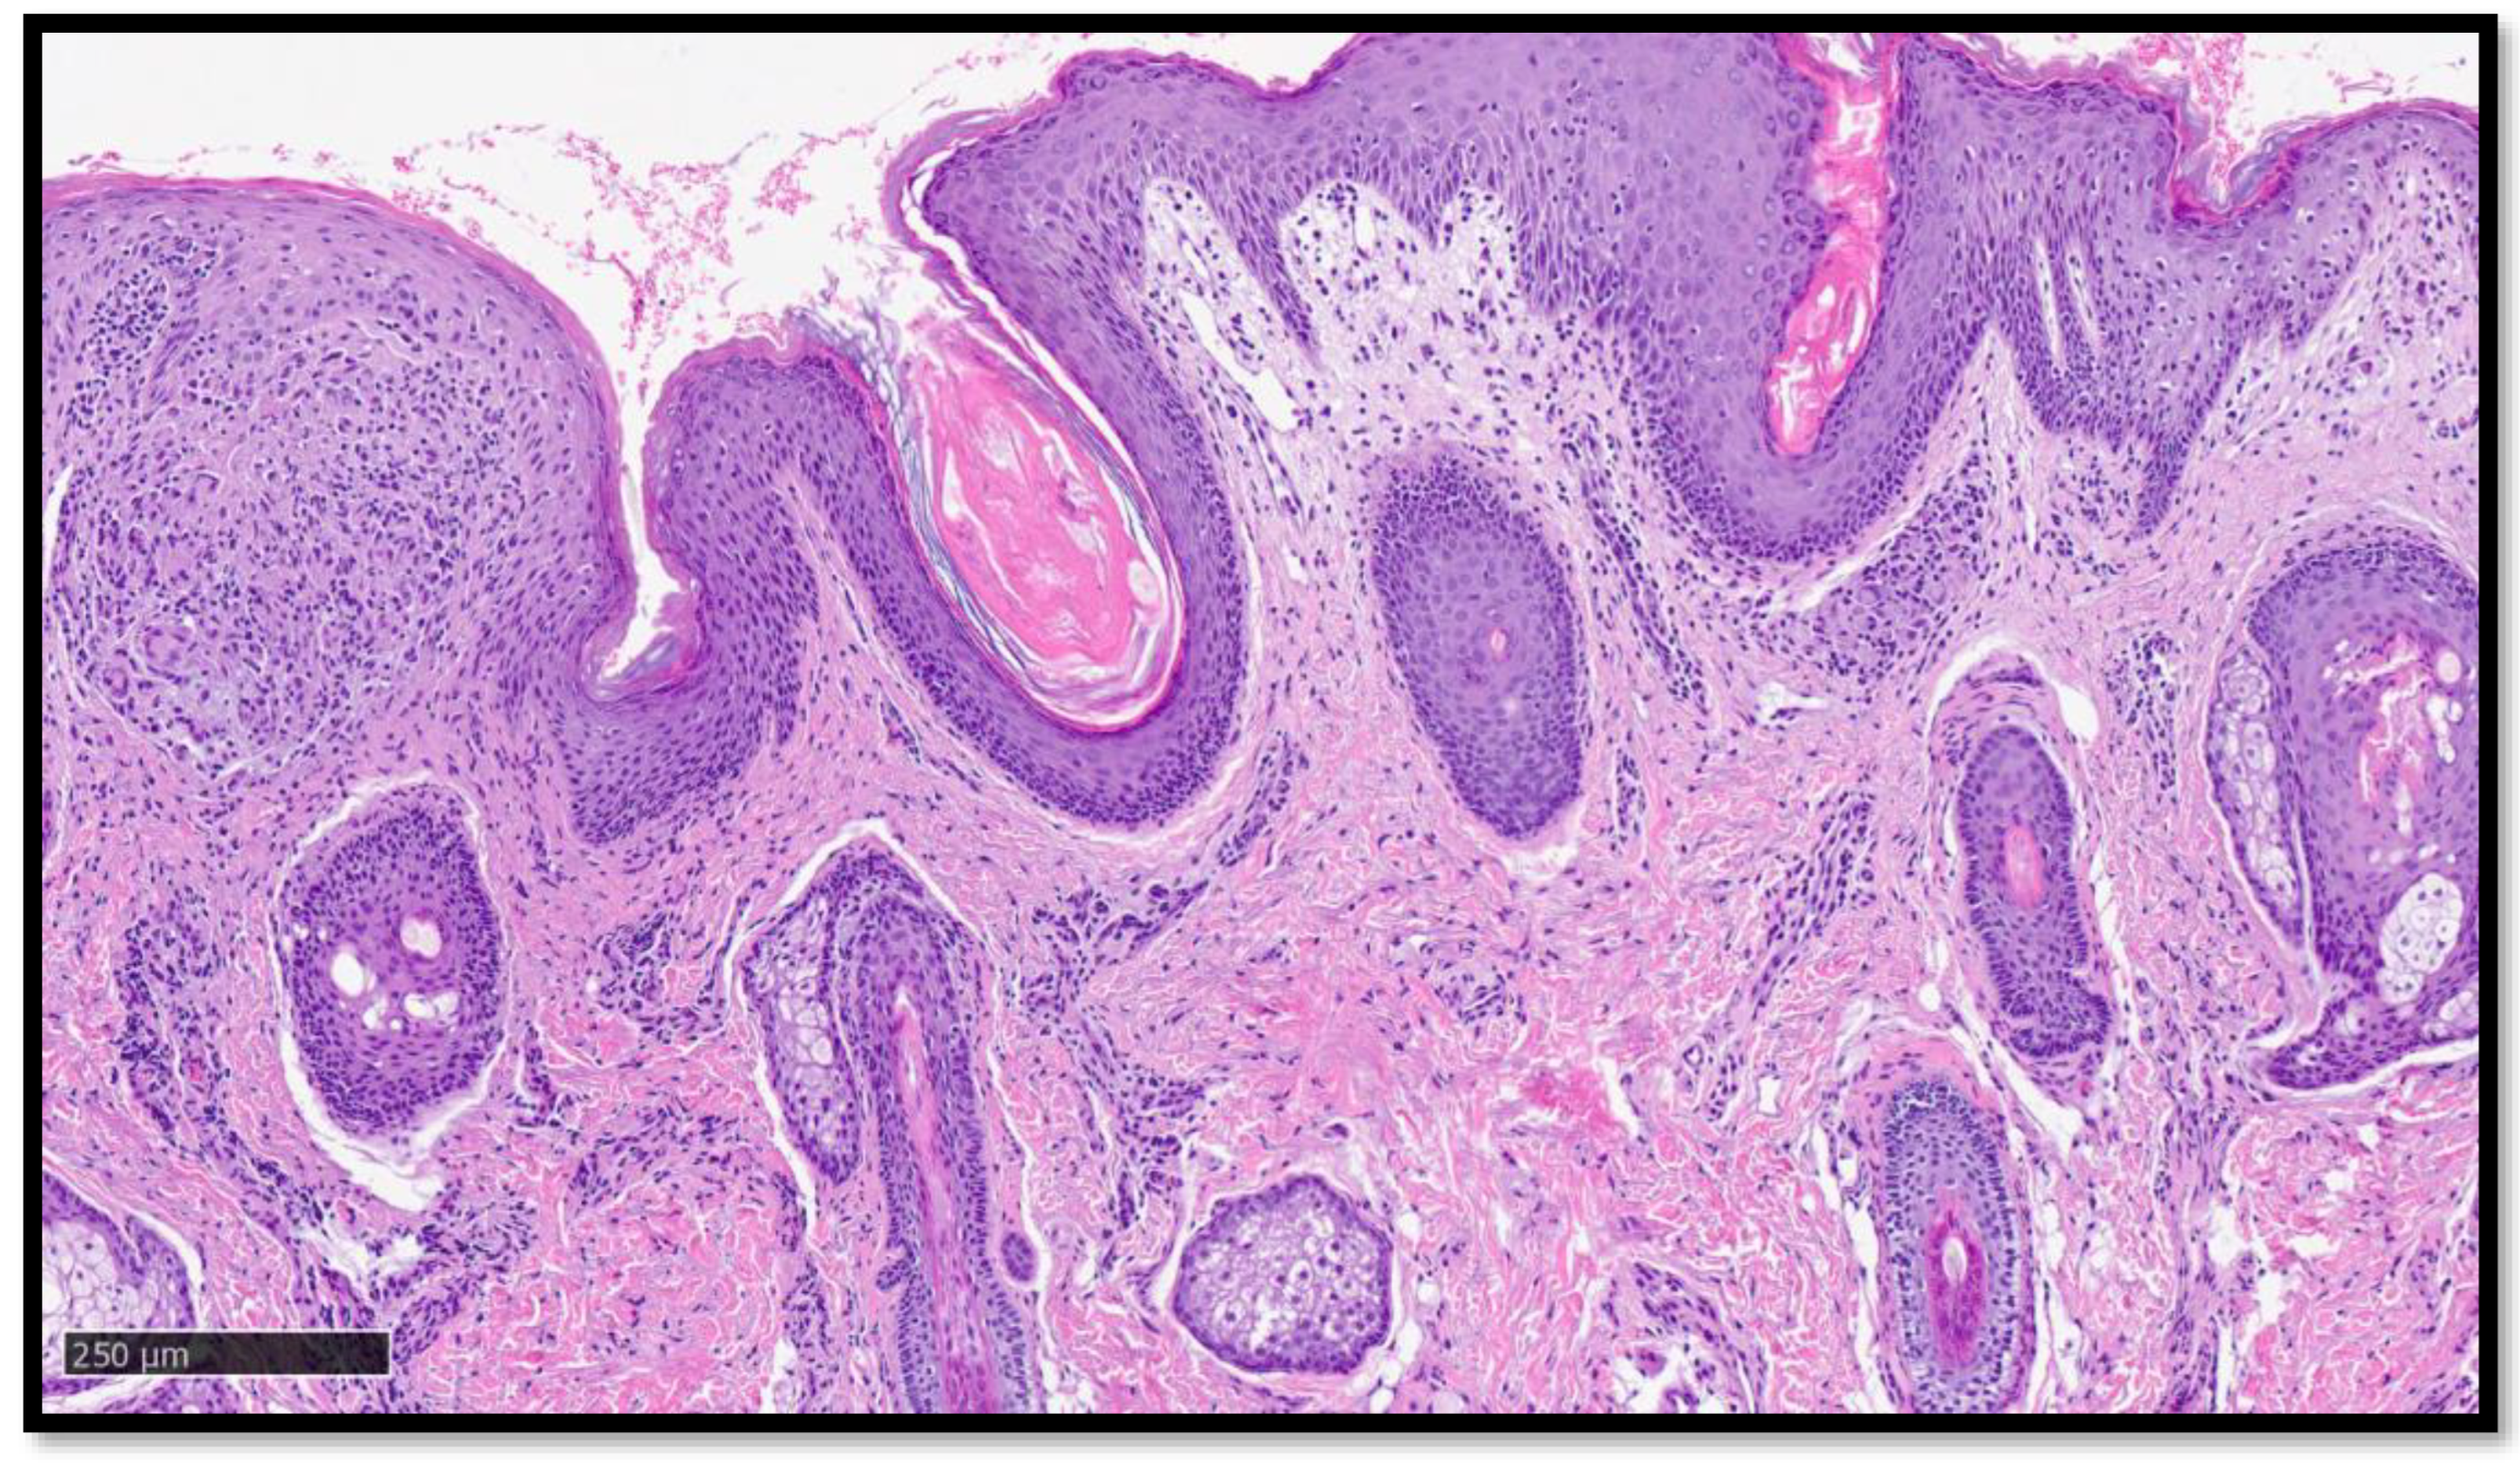

Cutaneous Sarcoidosis-like Eruption Following Second Dose of Moderna mRNA-1273 Vaccine: Case or Relationship?

Cazzato, G.; Ambrogio, F.; Foti, C.; Capuzzolo, M.; Trilli, I.; Casatta, N.; Lupo, C.; Carrieri, M.; Daini, D.; Colagrande, A.; et al. Cutaneous Sarcoidosis-like Eruption Following Second Dose of Moderna mRNA-1273 Vaccine: Case or Relationship? Diagnostics 2023, 13, 1286. https://doi.org/10.3390/diagnostics13071286